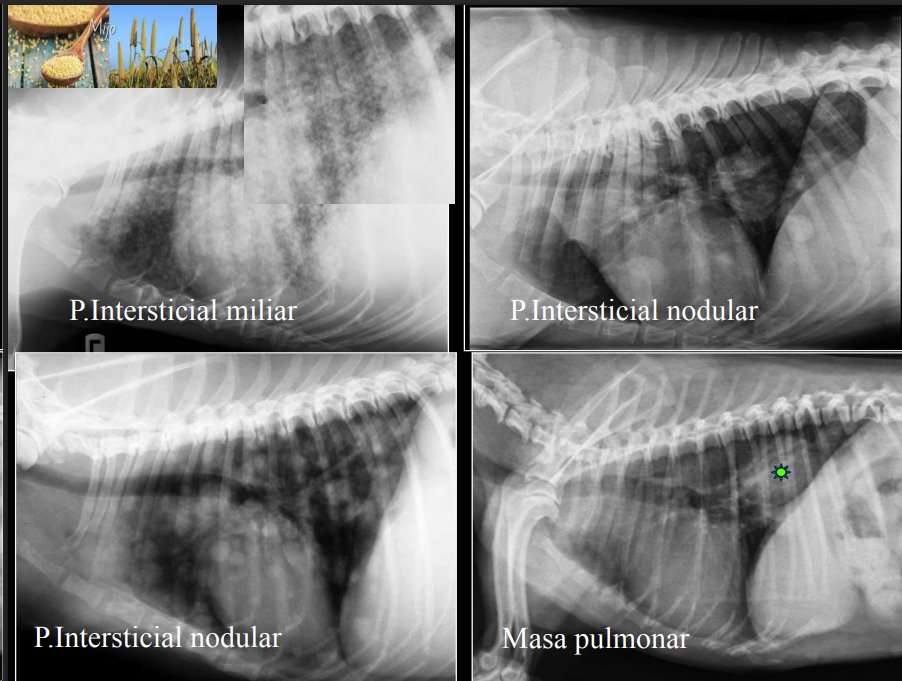

PATRÓN INTERSTICIAL

Nodular/Estructurado:

- Opacidades redondeadas (“miliar”, “nodular”, “masa”). A veces se puede confundir el patron miliar con calcificaciones (ocurren en pacientes mayores) pero estos tienen una mayor cantidad de radioopacidad al ser casi hueso.

- No confundir con patron miliar con los vasos transversales. Mas comunes cerca de la aorta, menos comun en la periferia del pulmon.

- patron heterogeneo de blancos y negros.

- Causas: metástasis, abscesos, tumores, granulomas.

- Se puede clasificar en estructurado o nodular y no estructurado o reticular.

Difuso/Reticular:

- Aumento lineal o reticular de opacidad.

- Causas: edema, neumonía, hemorragia, fibrosis (Comun en westies), linfosarcoma, leptospirosis, vasculitis.